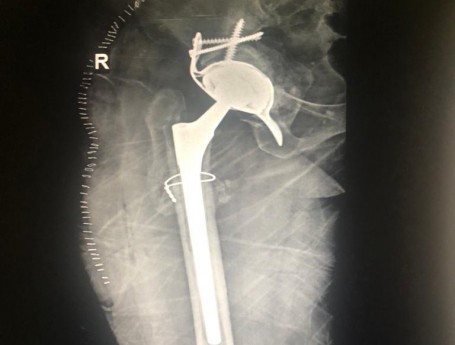

Revision Total Hip Arthroplasty

• Revision Total Hip Arthroplasty